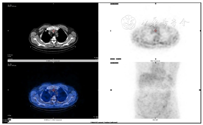

患者既往明确有2型糖尿病和高血压,入院后予皮下注射长效加餐时胰岛素降糖治疗,苯磺酸左旋氨氯地平和缬沙坦降压治疗。患者既往无慢性肾功能不全病史,本次入院初次发现慢性肾功能不全4期,既往无低钙抽搐病史,结合骨代谢指标提示患者高钙血症、高PTH,考虑诊断PHPT,但甲状旁腺超声未见明显异常,原发病灶尚不明确。考虑患者中度高钙血症,且临床症状明显,需给予降钙治疗,予生理盐水3 000 mL/d扩容、静推呋塞米(速尿)40 mg bid利尿和皮下注射鲑鱼降钙素100 IU tid促进尿钙排泄,降血钙治疗3天后血钙水平仍高,予单次静滴唑来膦酸4 mg治疗。胸部CT平扫提示前纵隔软组织影,予进一步完善18F-FDG全身代谢显像见前上纵隔软组织密度影,不伴明显代谢增高,良性病变可能性大,余处未见明显放射性异常浓聚区(图1)。结合胸部CT平扫和18F-FDG全身代谢显像结果,怀疑是否有胸腺瘤可能。因甲旁亢原发病灶仍不明确,需考虑是否有其他异位病灶。99mTc-MIBI双时相甲状旁腺显像示甲状腺下方、胸骨柄后方放射性异常浓聚灶,提示异位甲状旁腺伴功能亢进(图2)。行99mTc-MDP全身骨显像示左顶骨点状放射性摄取增高(图3)。因此,结合骨代谢指标及影像学表现,考虑诊断前上纵隔异位甲状旁腺腺瘤致PHPT。上腹部CT平扫:肝囊肿(12 mm×12 mm),胰腺未见明显异常,两侧肾上腺增生,右侧肾上腺髓样脂肪瘤可能(直径约15.5 mm),胆囊结石,左肾多发结石,右肾萎缩。胃泌素:59.89 pg/mL(25~100),血淀粉酶:81 U/L(28~100)。针对肾上腺相关内分泌激素检查:硫酸脱氢表雄酮、17-α羟孕酮、小剂量地塞米松抑制试验未见异常,立位肾素、血管紧张素、醛固酮指标正常,血儿茶酚胺水平正常。鞍区CT平扫见稍高密度影,但促肾上腺皮质激素及皮质醇节律、泌乳素、促性腺激素、胰岛素样生长因子1均正常,甲状腺超声提示甲状腺双侧叶结节TI-Rads 2类,甲状腺功能、甲状腺球蛋白、降钙素正常。降钙治疗6天后患者血钙水平降低至正常水平,考虑患者诊断为前上纵隔异位甲状旁腺腺瘤,定位明确且临床症状明显,手术切除异位腺瘤为最佳方案,患者出院后进一步于外院全麻下行胸腔镜纵隔内肿物切除术,纵隔内肿物:大小4.5 cm×3 cm×2 cm,病理诊断为:甲状旁腺腺瘤;免疫组化示:PTH(+),GATA(+),Rb(+),Bcl2(-),MDM2(+),CgA(+),Syn(-),CD56(-),Galectin3(-),CK(pan)(+),CK19(+),p63(-),CD34(血管+),Ki67(2%阳性)。术后第1天血钙为1.92 mmol/L,PTH为3.2 pmol/L。予10%葡萄糖酸钙20 mL/d静推,同时给予口服钙片和骨化三醇治疗,血钙逐渐恢复正常后出院。术后6个月后随访患者关节骨痛症状较前明显改善,肾功能较前明显好转,血尿酸425 μmol/L(143~420),血尿素6.7 mmol/L(2.5~6.4),血肌酐87 μmol/L(45~104),eGFR(CDK-EPI) 78 mL·min-1·(1.73 m2)-1(>90),血钙2.25 mmol/L,PTH为2.8 pmol/L,提示无甲状旁腺功能亢进复发。